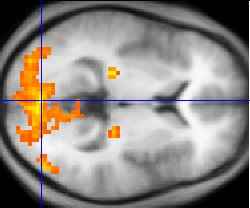

fMRI (Functional Magnetic Resonance Imaging) is a

technique for determining which parts of the brain are activated

by different types of physical sensation or stimuli such as sight,

sound or the movement of a subject's fingers. The brain

mapping is done by setting up an MRI scanner in a special way

so that the increased blood flow to the activated areas of the

brain shows up on Functional MRI scans. Compared to MRI,

fMRI does not depend on contrast agents although contrast

agents enable far greater detection sensitivity than BOLD

(Blood Oxygenation Level Dependent) signal. Higher BOLD fMRI picture

signal intensities arise from decreases in the concentration of

deoxygenated hemoglobin.

An fMRI experiment usually lasts 1-2 hours. The subject will lie in the magnet and a particular

form of stimulation will be set up and MRI images of the subject's brain are taken. In the first step a

high resolution single scan is taken. This is used later as a background for highlighting the brain areas

which were activated by the stimulus. In the next step a series of low resolution scans are taken over

time, for example, 150 scans, one every 5 seconds. For some of these scans, the stimulus will be

presented, and for some of the scans, the stimulus will be absent. The low resolution brain images in

the two cases can be compared, to see which parts of the brain were activated by the stimulus.

The rest of the analysis is done using a series of tools which correct distortions in the images,

remove the effect of the subject moving their head during the experiment, and compare the low

resolution images taken when the stimulus was off with those taken when it was on. The final statistical

image shows up bright in those parts of the brain which were activated by this experiment. These

activated areas are then shown as coloured blobs on top of the original high resolution scan. This image

can also be rendered in 3D.